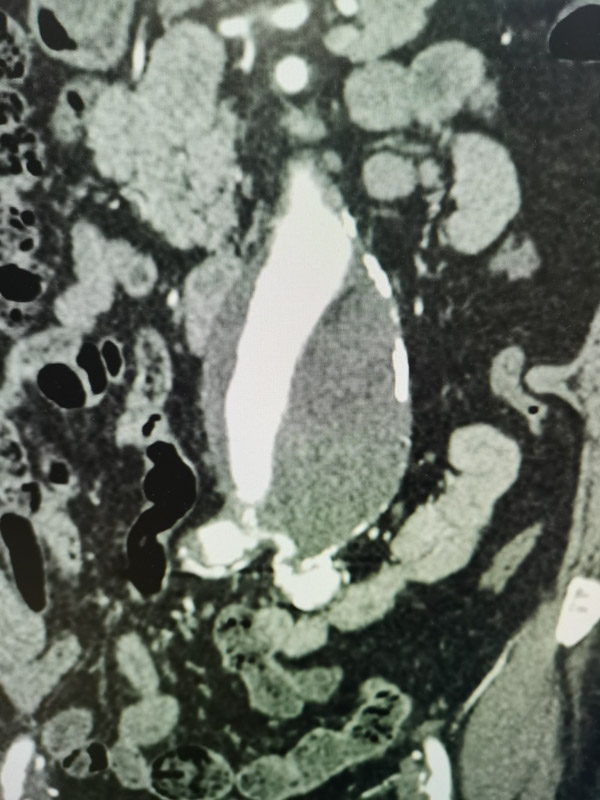

據(jù)我院心臟血管外科主任醫(yī)師陳俞宏介紹,腹主動脈瘤就像個膨大的氣球,只不過里面是流動的高壓血流。“氣球”在血流沖擊作用下越來越大,一旦破裂,就會發(fā)生致命性的大出血并在很短時間內(nèi)發(fā)生低血容量休克而導(dǎo)致死亡,十分兇險。該患者的情況比較復(fù)雜,因腹主動脈瘤瘤頸扭曲,入路狹窄閉塞,不適合介入支架治療,只能選擇開放手術(shù),且右髂外動脈已經(jīng)完全閉塞,所以需要先開通髂動脈血管,再將腹主動脈瘤切除并置換人工血管。按照傳統(tǒng)的手術(shù)方案,需要分兩次手術(shù)進行,一個手術(shù)做好后,要等患者恢復(fù)后才能實施第二次手術(shù)。為了減輕患者的痛苦,體現(xiàn)以病人為中心的理念,經(jīng)過多學(xué)科聯(lián)合診療討論,同意血管外科團隊提出的復(fù)合手術(shù)方案。在實時影像學(xué)的引導(dǎo)下,采用介入技術(shù)與傳統(tǒng)外科技術(shù)聯(lián)合治療,使原本需要多次的手術(shù),一次就能搞定,患者無需在介入室和外科手術(shù)室之間多次轉(zhuǎn)移, 提高了手術(shù)效率,避免二次麻醉,節(jié)省了醫(yī)療費用。

最終,血管外科團隊在最新的復(fù)合手術(shù)室中為其施以右髂動脈球囊血管成形術(shù)+右髂外動脈支架置入術(shù),經(jīng)精確測量,將一枚金屬裸支架植入右髂動脈開口處,術(shù)中造影復(fù)查發(fā)現(xiàn)右髂總動脈、髂外動脈恢復(fù)通暢。

隨后繼續(xù)進行腹主動脈瘤切除+人工血管置換術(shù),經(jīng)過三個多小時,手術(shù)順利結(jié)束,術(shù)后患者在重癥監(jiān)護室觀察一個晚上,次日即轉(zhuǎn)回血管外科病房繼續(xù)治療。